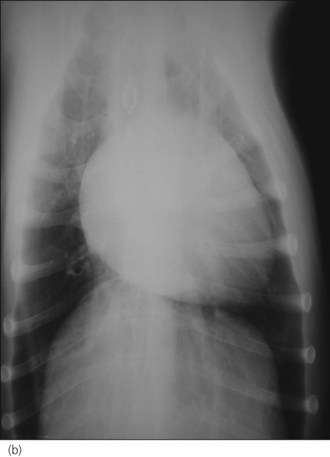

Case management

An intravenous catheter was placed into a cephalic vein and blood obtained via the catheter for an emergency database that was unremarkable. Continuous electrocardiogram monitoring was commenced and sinus tachycardia identified. Echocardiography confirmed the clinical suspicion of pericardial effusion (Figure 31.4).

Figure 31.4 Echocardiogram image of pericardial effusion visible as an anechoic space around the heart; both a collapsed right ventricle and the left ventricle are also visible.

(Photograph courtesy of Tobias Wagner)